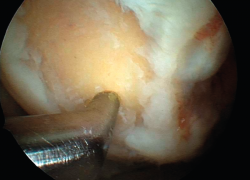

The results obtained with the microfracture techniques show variations, depending on the consulted literature source. This is due to the different hyaline characteristics of the regenerated cartilage. In some cases the percentage of fibrocartilage is high (Figure 2), due to a greater presence of type I collagen and the absence of type II collagen, in addition to the absence of a stratified cartilage tissue. Hyaline cartilage is characterized by the presence of type I collagen at the sliding surface, while type II collagen is the predominant form in the rest of the tissue, distributed to conform three basic stratification zones. These structural characteristics confer the biomechanical properties that allow long lasting function(13).

Figure 2. A: arthroscopic appearance of an ulcer with bleeding microfracture orifices; B: appearance of the same zone covered by fibrocartilage 8 months later.